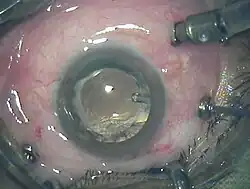

Витрэктомия — операция по удалению из глаза части или всего стекловидного тела. Передняя витрэктомия часто преследует цель удаления из передних структур глаза небольших кусочков стекловидного тела, застрявших там. Первичная витрэктомия — общий термин для группы операций, совершаемых в более глубоких частях глаза, которые включают в себя частичное или полное удаление прозрачного желе стекловидного тела.

Лэнсэктомия Архивная копия от 15 апреля 2021 на Wayback Machine — удаление хрусталика когда он мутный (катаракта), или если он скреплен с фиброзной тканью[3].